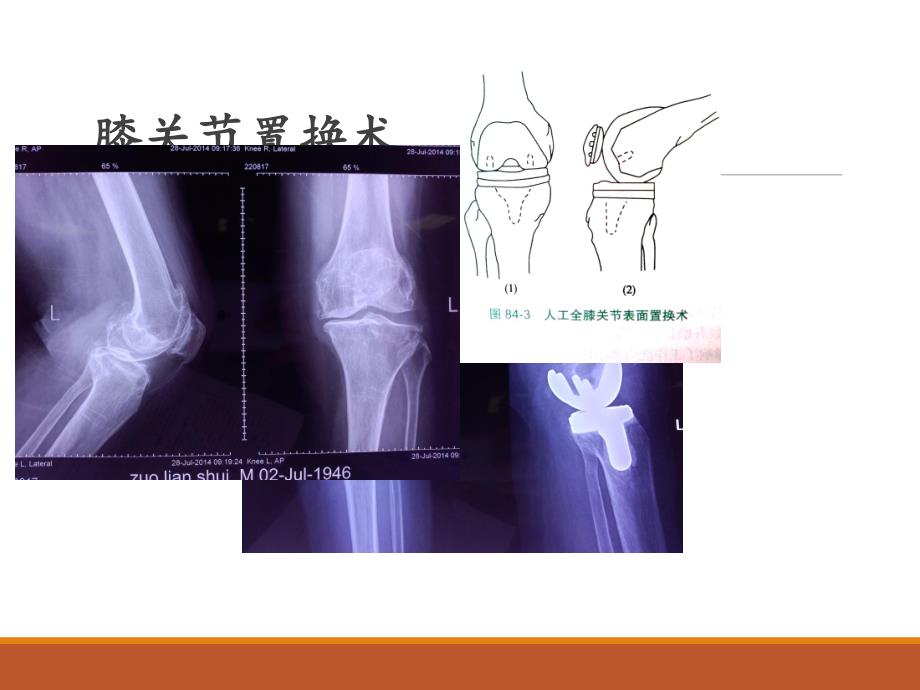

1、髋、膝关节置换术的适应症髋、膝关节置换术的适应症和并发症和并发症膝关节置换术膝关节置换术膝关节置换术的适应症膝关节置换术的适应症(三关节(三关节间室型)间室型)解除因严重关节炎而引起的疼痛,无论是否合并有明显的畸形。年龄较大的,有较多坐立生活习惯的患者。年轻的但因关节炎致多关节受累并造成功能障多关节受累并造成功能障碍碍的患者。类风湿性关节炎、痛风性关节炎、血友病性关节炎、大骨节病双侧膝关节骨关节炎,双膝关节单髁置换术膝关节置换术的并发症膝关节置换术的并发症 1、术后疼痛 2、深静脉栓塞 3、切口愈合不良 4、假体松动 5、假体周围感染 6、胫骨假体周围骨折 7、股骨假体周围骨折 8、髌骨骨折